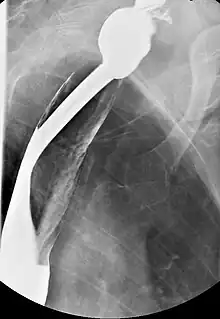

Serial contrast gastrointestinal radiography or upper-gastrointestinal endoscopy may reveal the presence of esophageal webs. Blood tests typically show hypochromic microcytic anemia, consistent with iron-deficiency anemia. A biopsy of the affected mucosa usually reveals epithelial atrophy (shrinking) and varying degrees of submucosal chronic inflammation. Epithelial atypia or dysplasia may also be present. In some cases, the syndrome may manifest as post-cricoid malignancy, which can be detected by the absence of laryngeal crepitus. Normally, laryngeal crepitus is produced when the cricoid cartilage rubs against the vertebrae.

Barium esophagography and videofluoroscopy can aid in detecting esophageal webs. Esophagogastroduodenoscopy allows for the visual confirmation of these webs, which are caused by subepithelial fibrosis.